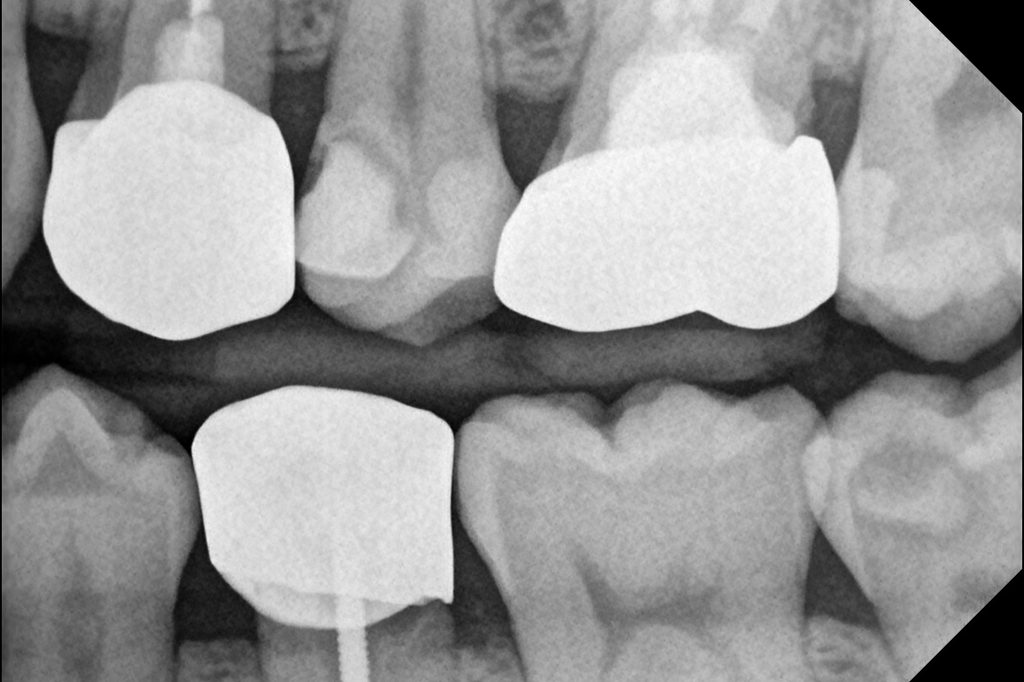

오늘 소개드릴 케이스는 왼쪽 위 작은어금니(제2소구치, #25)에 깊은 충치가 발생하여 내원하신 환자분입니다. 육안으로도 확인되는 충치 병소가 있었으며, 치료 과정에서 예상치 못한 치수 노출이 발생했습니다.

환자분은 특별한 통증 증상 없이 내원하셨으며, 방사선 검사 결과 치근단에 병소는 관찰되지 않았습니다. 다만 우식이 치수에 매우 근접해 있어 치료 중 치수 노출 가능성을 염두에 두고 신중하게 접근했습니다.